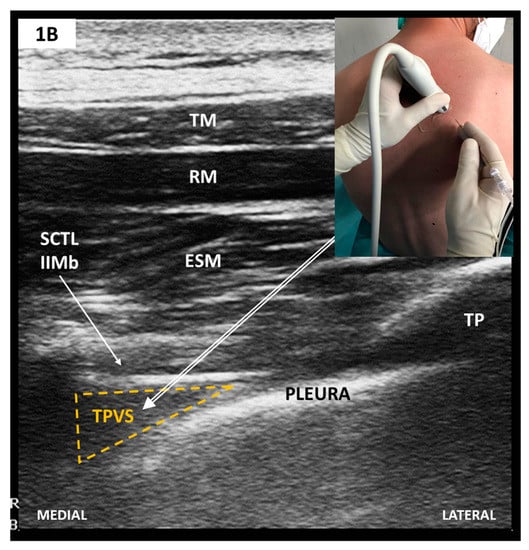

2.2. Paravertebral Blocks (PVB)

Sonoanatomy and Block Techniques (Figure 1)